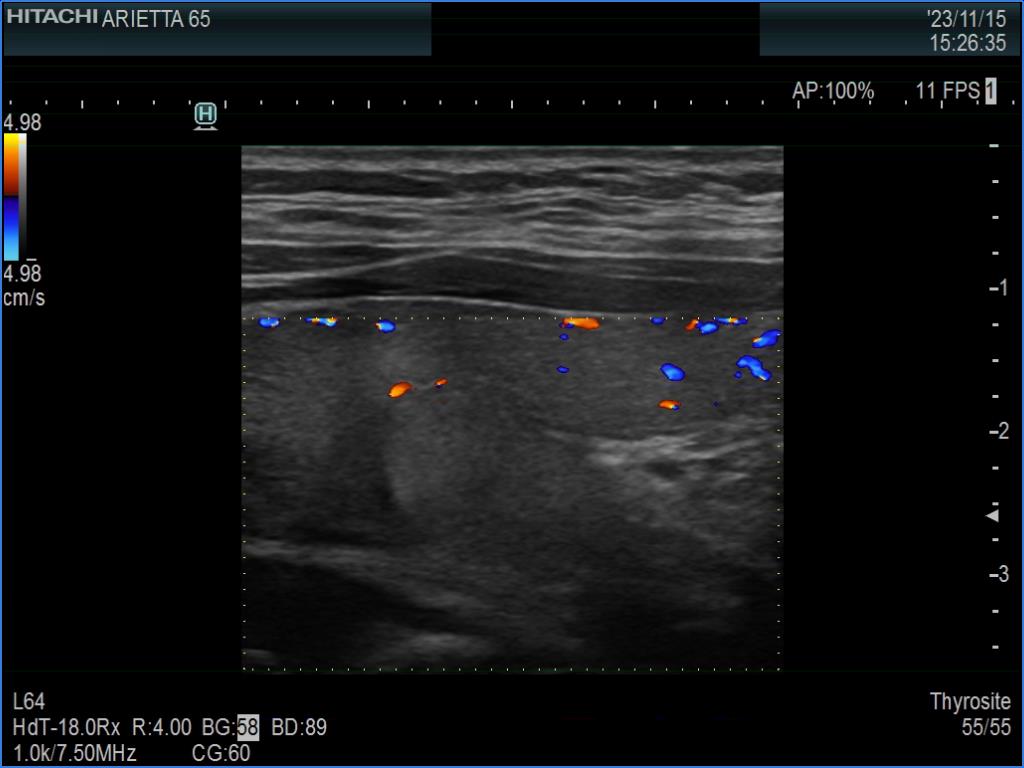

Ultrasonography. The thyroid was minimally hypoechoic. The echogenicity of the dorsal part of the left lobe where the nodule was previously described did not differ from other parts of the thyroid. There was a connective tissue running ventral to this part of the lobe and hypoechoic areas were found upper and dorsal to this. Neither halo nor perinodular blood flow was present.

The area in question did not correspond to a pathological nodule. It seemed to be circumscribed because of the presence of connective tissue and thyroid vessels.

A follicular tumor must have a capsule which ultrasound sign, either a complete halo and/or perinodular blood flow are present in more than 95% of cases. Both features were absent in this case.